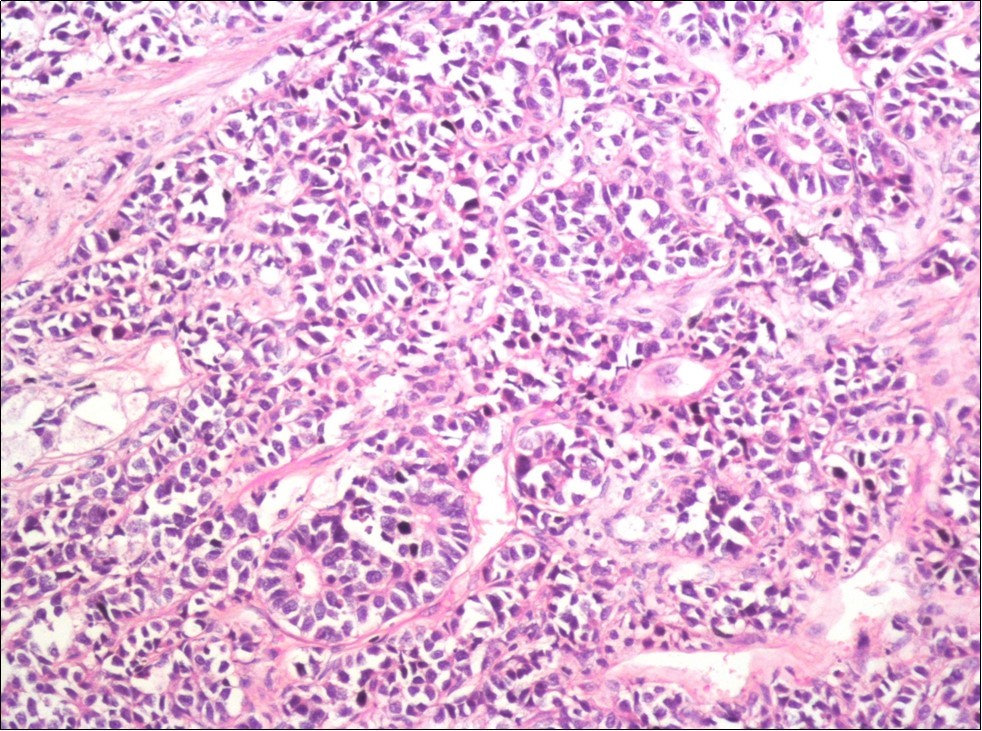

A 73-year-old male patient was admitted to our outpatient clinic with acute urinary retention. Digital rectal examination was normal. The PSA value was 1.81 ng/dl. Prostate size was 101 cc. Since the PSA value and digital rectal examination were normal, no biopsy was taken. Ultrasonography showed bilaterally ureterohydronephrosis. The creatinine level was 2.89 mg/dl. Hypertension has been presented as a comorbidity. An 18 Fr Foley catheter was inserted and alpha-blockers and 5-α reductase inhibitor medication was given. Creatinine level decreased to 0.91 mg/dl after one week. When the patient's catheter was pulled out, he could not urinate again. A catheter was inserted and waited one week more. After one week, the patient was unable to urinate again. The operation was decided due to this recurrent urinary retention. Because of prostate size was 101 cc and prostatic urethra was long, open prostatectomy was decided. When the prostate was removed during the operation, it was evaluated that the left side and the lower side were adhered to surrounding tissue. The prostate was removed as an en bloc. The catheter was removed after 5 days. The pathology of the patient has been reported as pure small cell prostate carcinoma. On the microscopic examination, the tumor was heavily infiltrated into the prostate parenchyma (Figure 1). Tumor cells were consist of atypical small-medium sized, mitotically active cells with a high nuclear to cytoplasmic ratio, hyperchromatic nucleus, nuclear molding, and inconspicuous nucleoli (Figure 2). On the immunohistochemically examination of synaptophysin showed diffusely and strong positivity while chromogranin A showed focal weak positivity with the absence of staining for PSA (Figure 3). Ki67 proliferative index was equal to 90% of the tumor cells (Figure 4). The results confirmed the diagnosis of prostatic small cell carcinoma. Metastatic lymph nodes were detected in the right perirectal region with metastatic multiple lymph nodes in the bilateral external iliac region, more on the left than in the PET CT. No metastasis was detected in the brain MRI and thorax computed tomography. Four cycles of etoposide and cisplatin chemotherapy were administered to the patient. Control PET CT taken after chemotherapy showed a significant decrease in size and metabolic activity of the right obturator and lymph nodes in the right perirectal area. The size and metabolic character of the left obturator, left external iliac and common iliac lymph nodes were increased. After a month, patient admitted to emergency outpatient clinic with left flank pain. There was an 8-cm mass in retroperitoneal area in the computed tomography. Supportive treatment was started because the patient could not tolerate chemotherapy. The masses reached to 13x11cm and fulfilled the retroperitoneal area. Multiple lung metastases were seen. The patient died 13 months later after the first diagnosis.

Figure 2.The tumor cells show rosette formation with hyperchromatic nuclei and nuclear molding (H&E, x200)